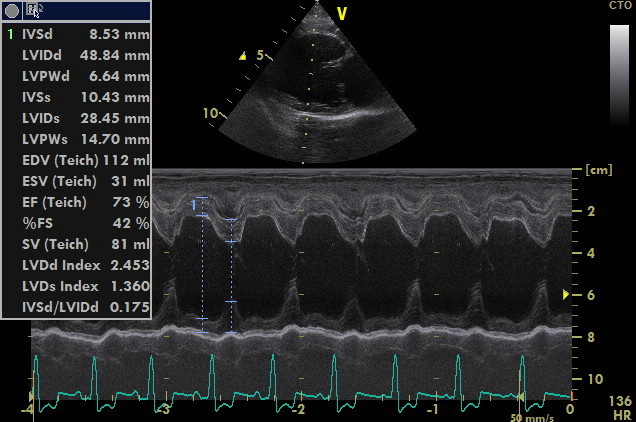

Herzultraschall

Durch die Herzultraschalluntersuchung konnte dann leider der Verdacht auf eine deutlich weiter fortgeschrittene Herzerkrankung bestätigt werden. Neben einer hochgradigen Vergrößerung der linken Herzhälfte durch die Klappeninsuffizienz ließ sich außerdem ein moderat erhöhter Druck in den Lungenarterien feststellen. Dies nennt man Pulmonale Hypertension oder Lungenhochdruck. Für eine solche Erhöhung des Blutdruckes im Lungenkreislauf gibt es unterschiedliche Ursachen. Eine davon ist ein bestehendes Lungenödem durch ein Linksherzversagen, wie es bei Alf nun offensichtlich der Fall war. Da die Diagnose nun „dekompensierte Mitralklappenendokardiose“ - oder nach der CHIEF - Klassifizierung Stadium C2 * - lautete, verordnete ich dem kleinen Hund zusätzlich zwei weitere Medikamente zur dauerhaften Herztherapie (eines zur Entwässerung und das andere zur Entlastung des Herzens durch Weitstellung der Arterien und zur Unterstützung der Pumpfunktion des Herzmuskels). Die am Morgen im Wald aufgetretene „Synkope“ ließ sich also eindeutig durch die fortgeschritten Herzerkrankung erklären.